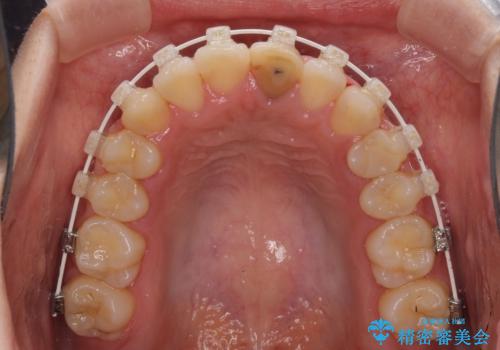

前歯の反対咬合 非抜歯のワイヤー矯正

- 審美装置

マウスピース矯正の自己管理が面倒くさいことと、治療を早く終わらせたいとのことで、目立ちにくいワイヤー矯正にて歯列を整えることとしました。

1年半はかかると思っていた治療期間ですが、反対咬合となっている前歯が思いの外早く動き、僅か9ヶ月で終了させることができました。